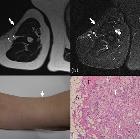

spectrum of abnormal subcutaneous and visceral fat distribution. A 59-year-old woman with post blunt trauma lipoatrophy on the right upper arm. a Axial T2-weighted and (b) STIR images show thinning of subcutaneous fat on the lateral aspects (arrows) with multiple high signal nodules (small arrows) showing small peripheral fat signal areas. c Photograph shows thinning of the lateral aspect of the upper arm with small hump (arrow). d Histologically fat necrosis with lipogranuloma was proven. Variably sized lipid vacuoles are surrounded by foam cells, foreign body-type (arrows), and Touton giant cells (arrowhead) in the resected lipogranuloma. A adipocytes, F fibrosis (hematoxylin-eosin stain, × 100)